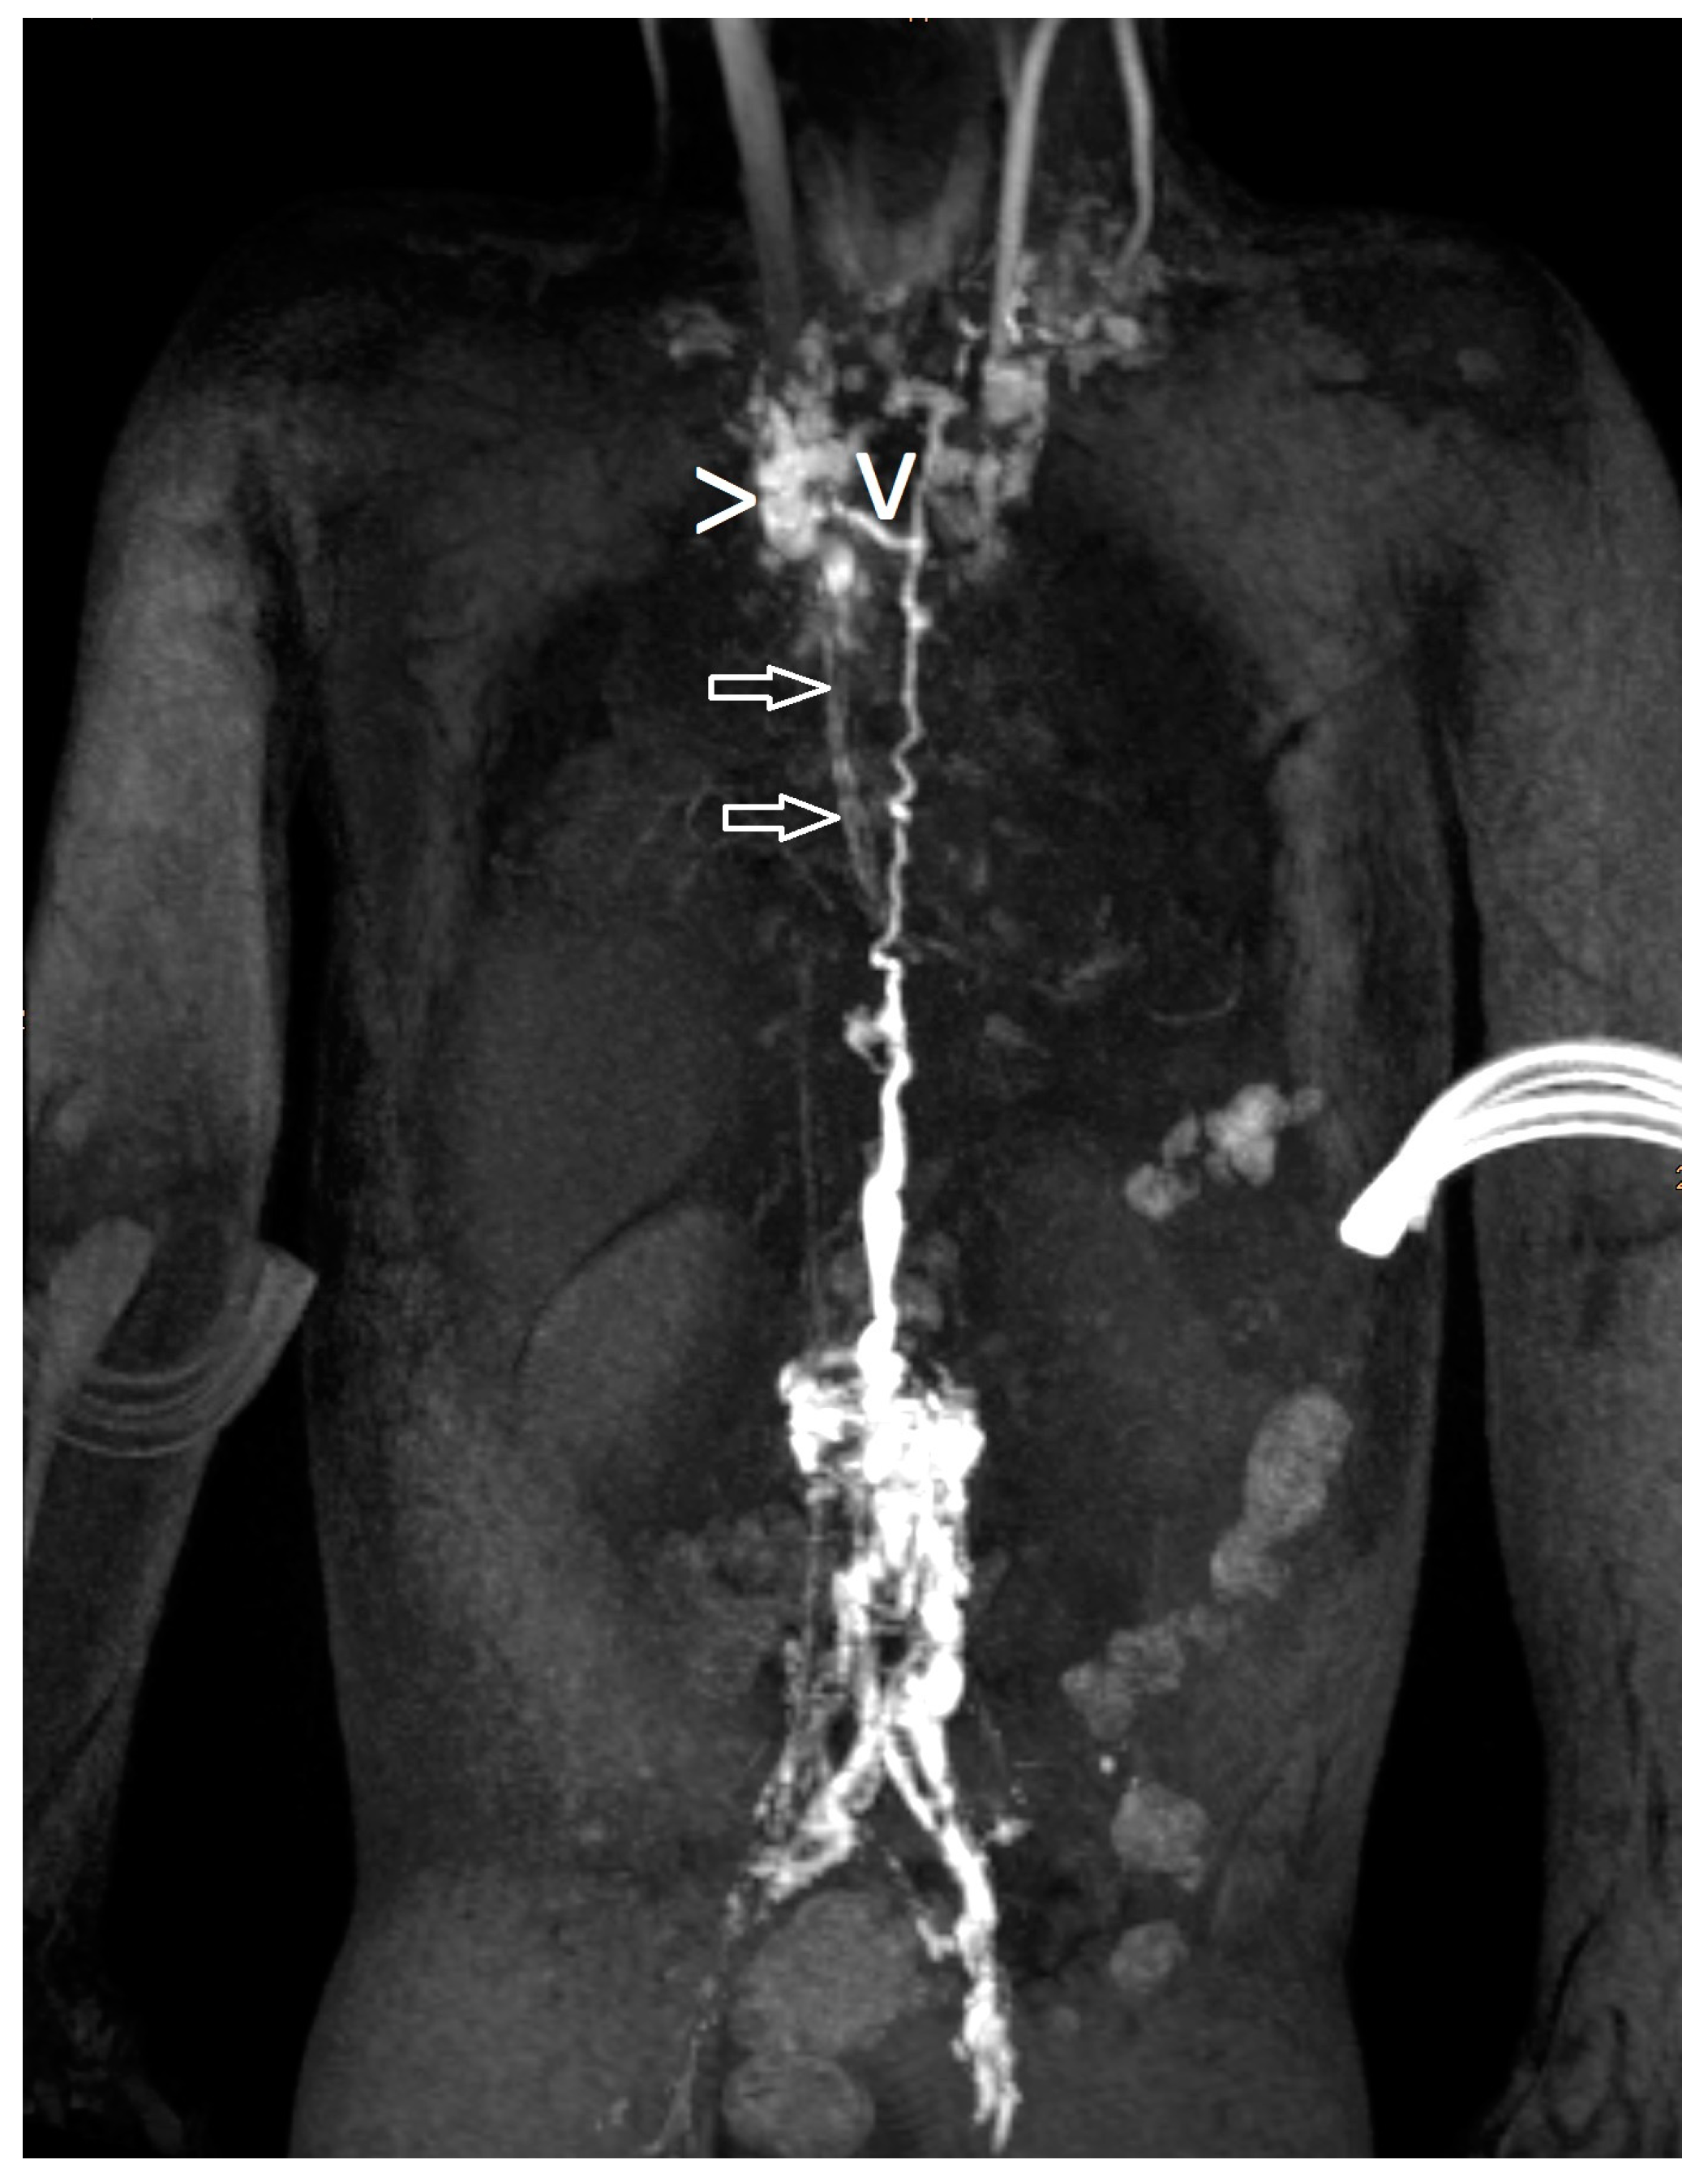

Figure 2.

Lymphatic fistula (“>” points to the distinct structure, “v” is the fistula and the arrows show another lymphatic network).

Lymphatic fistulas (Figure 2) were described when there was a distinct structure with retrograde flow depicted on dynamic contrast MR lymphangiography.